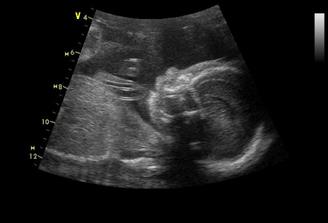

°°°°6.3.tak nás pustili domkov na priepustku,musíme sa ukázať 13.3.na kontrolu,sice nám zistili kvasinky,ale dali nám vagin.lieky na týždeň,tak verím,že piatok 13teho bude šťastný 🙂,inak na kontrolnom uzv sme videli,že hematom je už polovičný,čo je úžasné,pani doktorka mi prcka zase zmerala a ukázala orgány,keď sa dostala ku stehennej kosti a močovému mechúru,tak sme zistili,že máme nestydu 🙂,pani dr.sa smiala,že už chápe,prečo tak rozťahuje nožičky,ukazuje nám totiž hrdo,na čo je pyšný 🙂 °°°°budeme mať CHLAPČEKA 🙂°°°°

11.6.nás čaká ďalšia poradňa a veĺký ultrazvuk,aby sme vedeli,koľko ten náš macík váži 🙂 tak Samko je hlavičkou dole,váži 1598g a všetko je v poriadku,zobrali nám krvičku na protilátky,tak verím,že to dopadne dobre,čípok nezmenený a hrdlo stále uzatvorené 🙂už teraz mi dáva slušné kopance a je to niekedy až neuveriteĺné,čo predvádza,keď naňho hovorí tatino 🙂